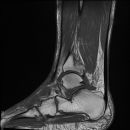

Talus Fraktur